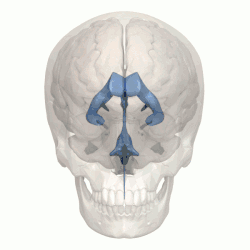

3D rendering of ventricles (lateral and anterior views)

The system comprises four ventricles:[5]

Ventricles

The four cavities of the human brain are called ventricles.[6] The two largest are the lateral ventricles in the cerebrum, the third ventricle is in the diencephalon of the forebrain between the right and left thalamus, and the fourth ventricle is located at the back of the pons and upper half of the medulla oblongata of the hindbrain. The ventricles are concerned with the production and circulation of cerebrospinal fluid.[7]